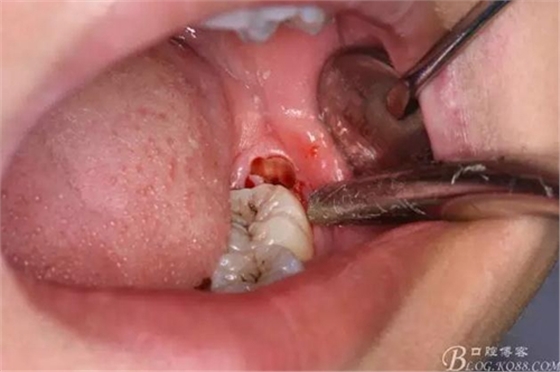

圖5.分離舌側(cè)牙齦

圖6.分離頰側(cè)牙齦,目的使牙冠和牙根能順利從牙齦軟組織脫位。